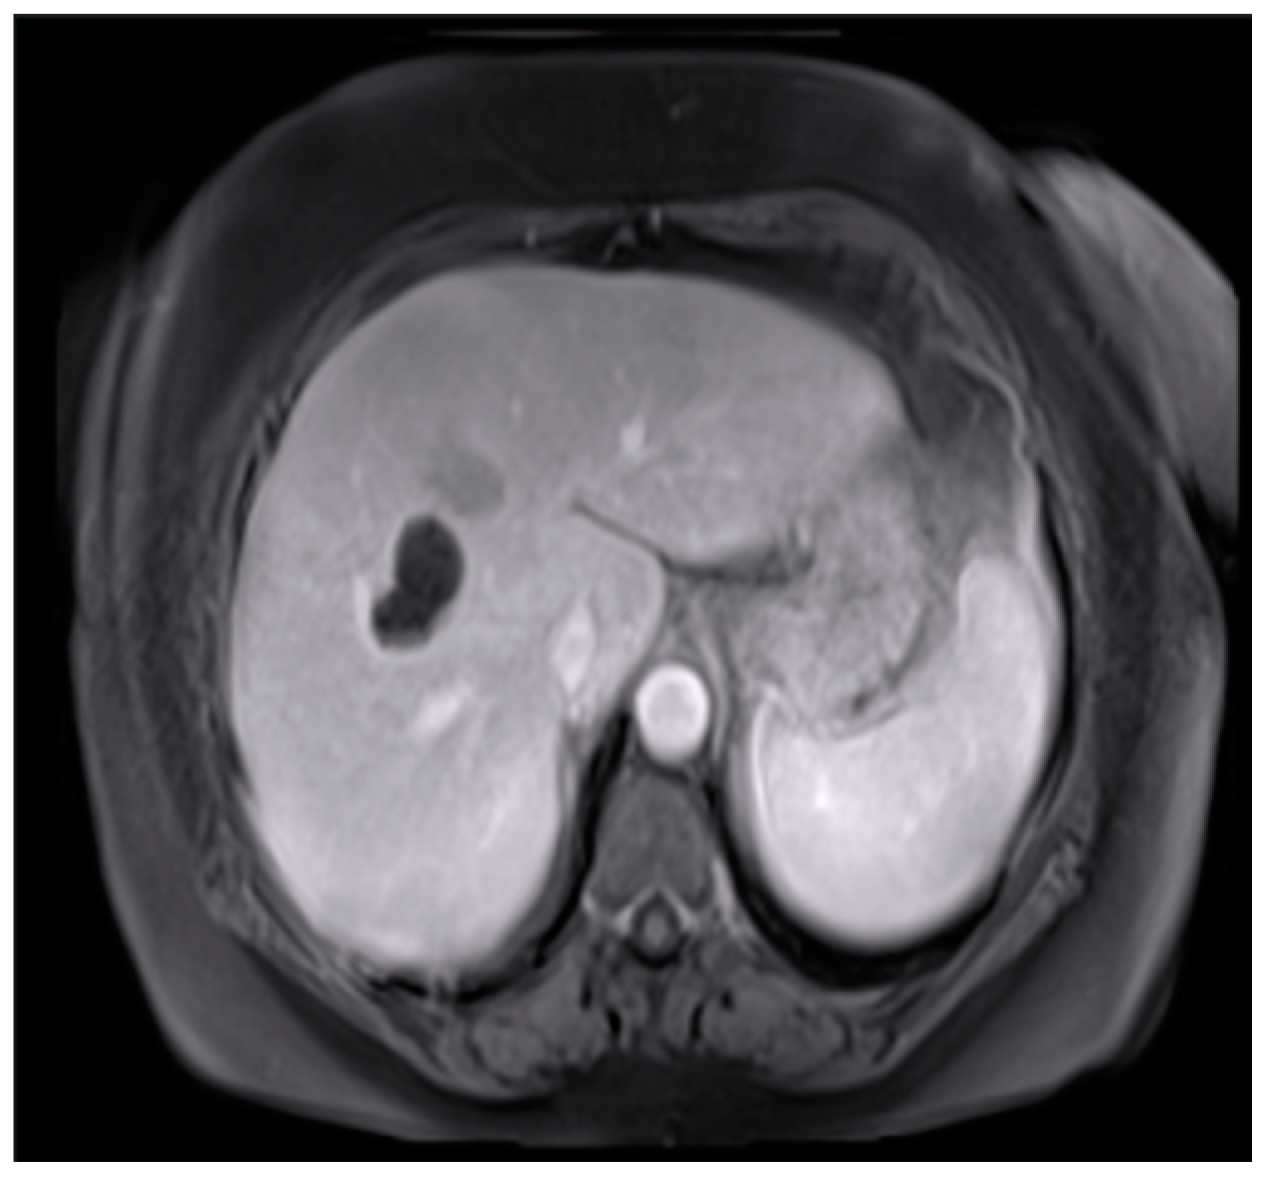

2.1. Image Dataset

The dataset utilized in this study was the cancer genome atlas liver hepatocellular carcinoma (TCGA-LIHC) data [4]. We related cancer phenotypes to genotypes by providing clinical images of TCGA [5]. Clinical, genetic, and pathological data were obtained from the Genomic Data Commons (GDC) data portal, while the radiological data were collected from TCIA. The original image size was 256 × 256 pixels and extracted to conduct preliminary testing and analysis (Figure 3). Figure 3 showcases the practical application of the processing techniques on the dataset [6].

Figure 3. Original image.